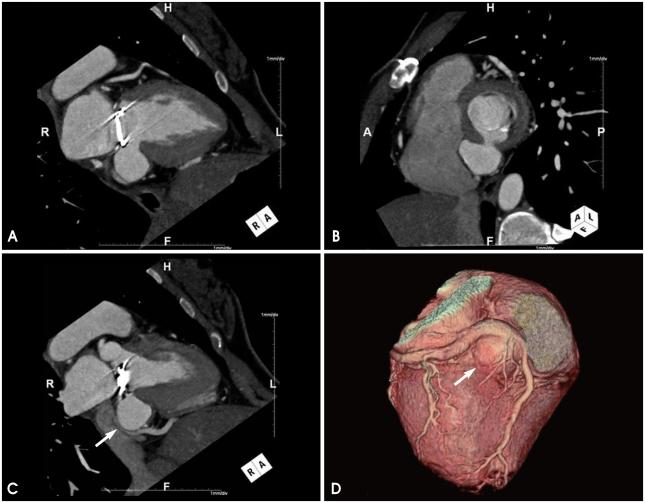

A case of left ventricular pseudoaneurysm in the left atrioventricular groove after mitral valve replacement.

Left ventricle-coronary sinus fistula and left ventricular pseudoaneurysm are unusual and frightening complications after mitral valve replacement. A 27-year-old female patient underwent mitral valve replacement 5 years previously and trans-thoracic echocardiography showed an outpouching lesion at the atrioventricular groove. It was difficult to differentiate whether the lesion was a left ventricle-coronary sinus fistula or a left ventricular pseudoaneurysm by two-dimensional echocardiography. Cardiac computed tomography confirmed a left ventricular pseudoaneurysm compressing the coronary sinus.